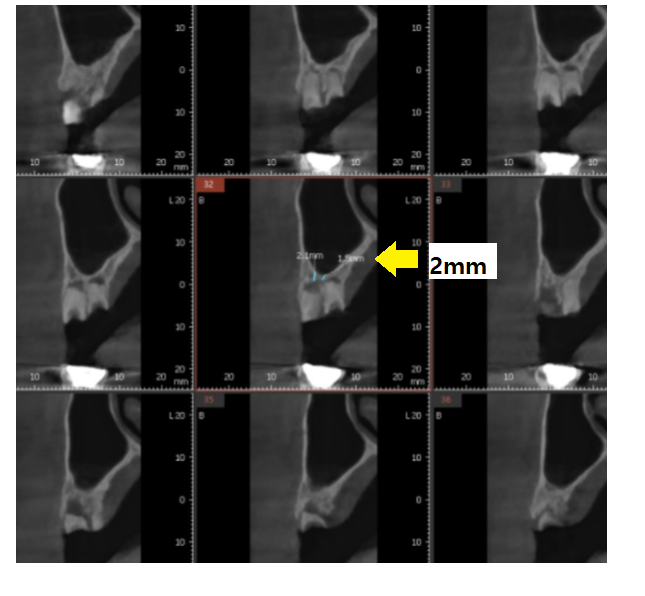

환자분도 2mm 정도 남아 있어서

(일반적으로 임플란트는 8mm정도 필요합니다)

23.12.30

상악동을 들어올리고

뼈 이식을 한뒤

풍산동 임플란트가 필요했습니다.